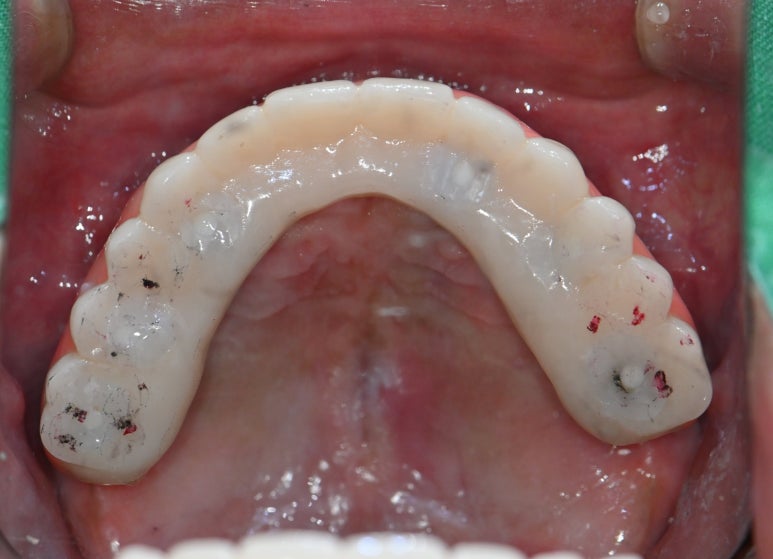

디지털 풀아치 임플란트가 완성된 모습

최종 완성된 디지털 풀아치 임플란트 (상악)